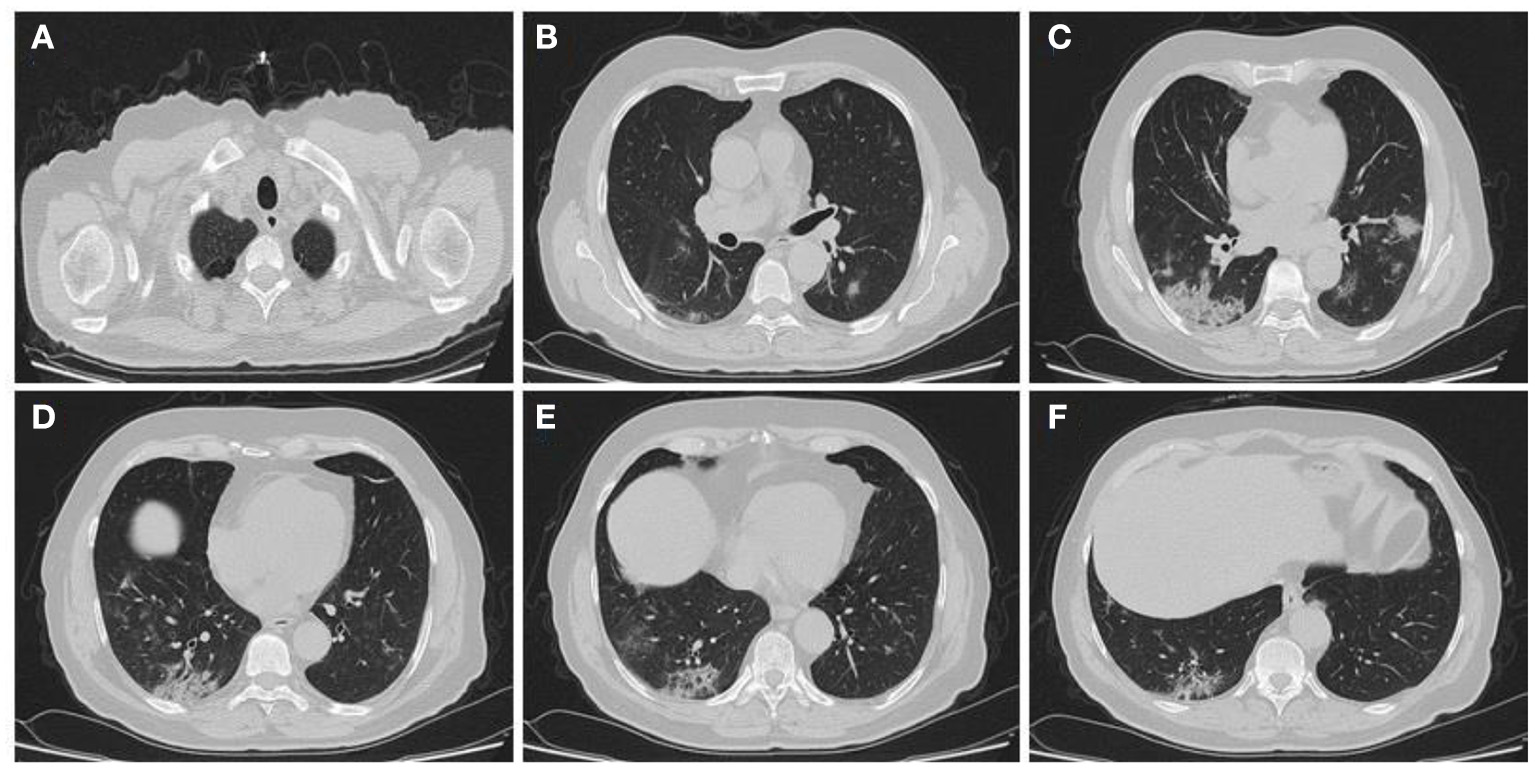

In the present study, 160 males and 70 females were enrolled to explore the association of lung CT findings in COVID-19 with patients' age, body weight, vital signs, and medical regimen. The reported major lung CT scan findings were GGO in 47 (20.4%) patients; calcified nodules in 3 (1.3%) patients; atelectasis and fibrotic band in 16 (7.0%) patients; pleural effusion and consolidation in 22 (9.6%) patients; infiltration and pneumonia in 11 (4.8%) patients; and emphysematous changes in 11 (4.8%) patients of the study sample (230 participants). Three different cases with major lung changes are shown in Figures 1–3. However, one case with minor lung CT scan findings is shown in Figure 4.

Figure 1. High resolution, axial non-enhanced spiral chest CT images (lung window) of a 69-years old patient who was confirmed to be infected by COVID-19 and admitted to hospital with fever and dry cough. CT images show (A) emphysematous changes in the apices of both lungs and multiple patchy consolidations predominantly in the lower lobe of the right lung (B–F).